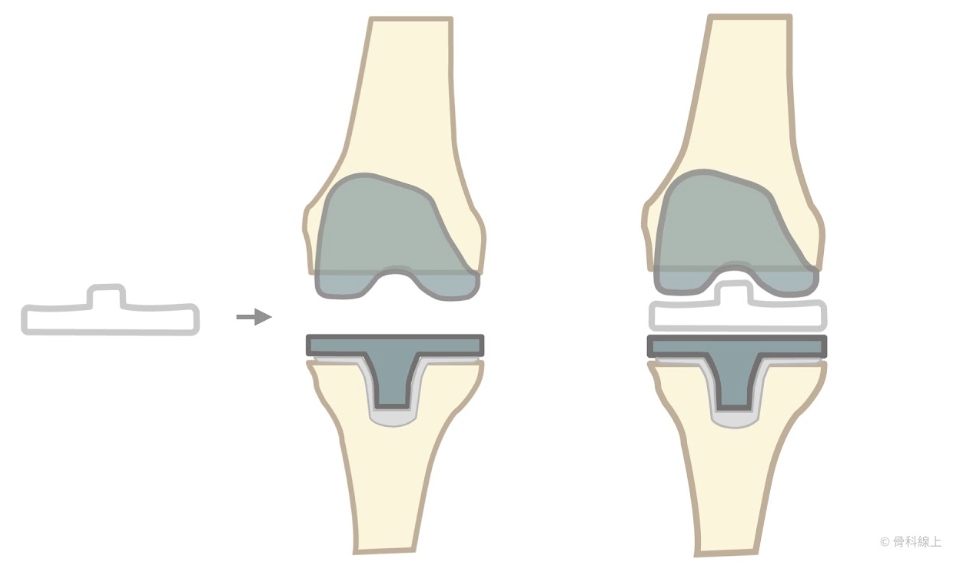

在說明人工膝關節置換手術之前,我們先畫個圖來了解人工膝關節手術怎麼裝。我們常這樣解釋:裝人工膝關節,就像是套牙套一樣,藉由裁切掉磨損的軟骨以及少量的骨頭來達到正確的膝關節角度,經過裁切的骨頭表面會和人工膝關節零件完全契合,再利用骨水泥將膝關節組件裝上裁切好的骨頭,就像拼裝拼圖一樣。

“所以,骨頭要切掉很多嗎?”事實上,下面的圖片顯示深色的部分,為裁切掉的骨頭的部分,其最厚的厚度大約也僅在 1 公分上下,整體而言相當少。

藉由裁切掉深色的骨頭部分,可以達到預計達到的角度(約外翻六度,就是有點 X 型腿的角度),再把膝關節股骨組件“套”上去。

除了正面之外,側面也有需要裁切的部分,股骨組件和骨頭之間,要藉由骨水泥來協助固定。

一般而言,脛骨的裁切的預計角度是完全水平,也就是與脛骨長軸垂直(既不內翻也不外翻),然後再用器械在脛骨做出一個凹槽,脛骨組件和凹槽呈現卡榫結合狀態,一樣使用骨水泥協助固定。

除了角度正確,要達到膝關節穩定的結果,就要選擇適當的墊片厚度,塞進股骨和脛骨組件之間,取得正確的鬆緊度。